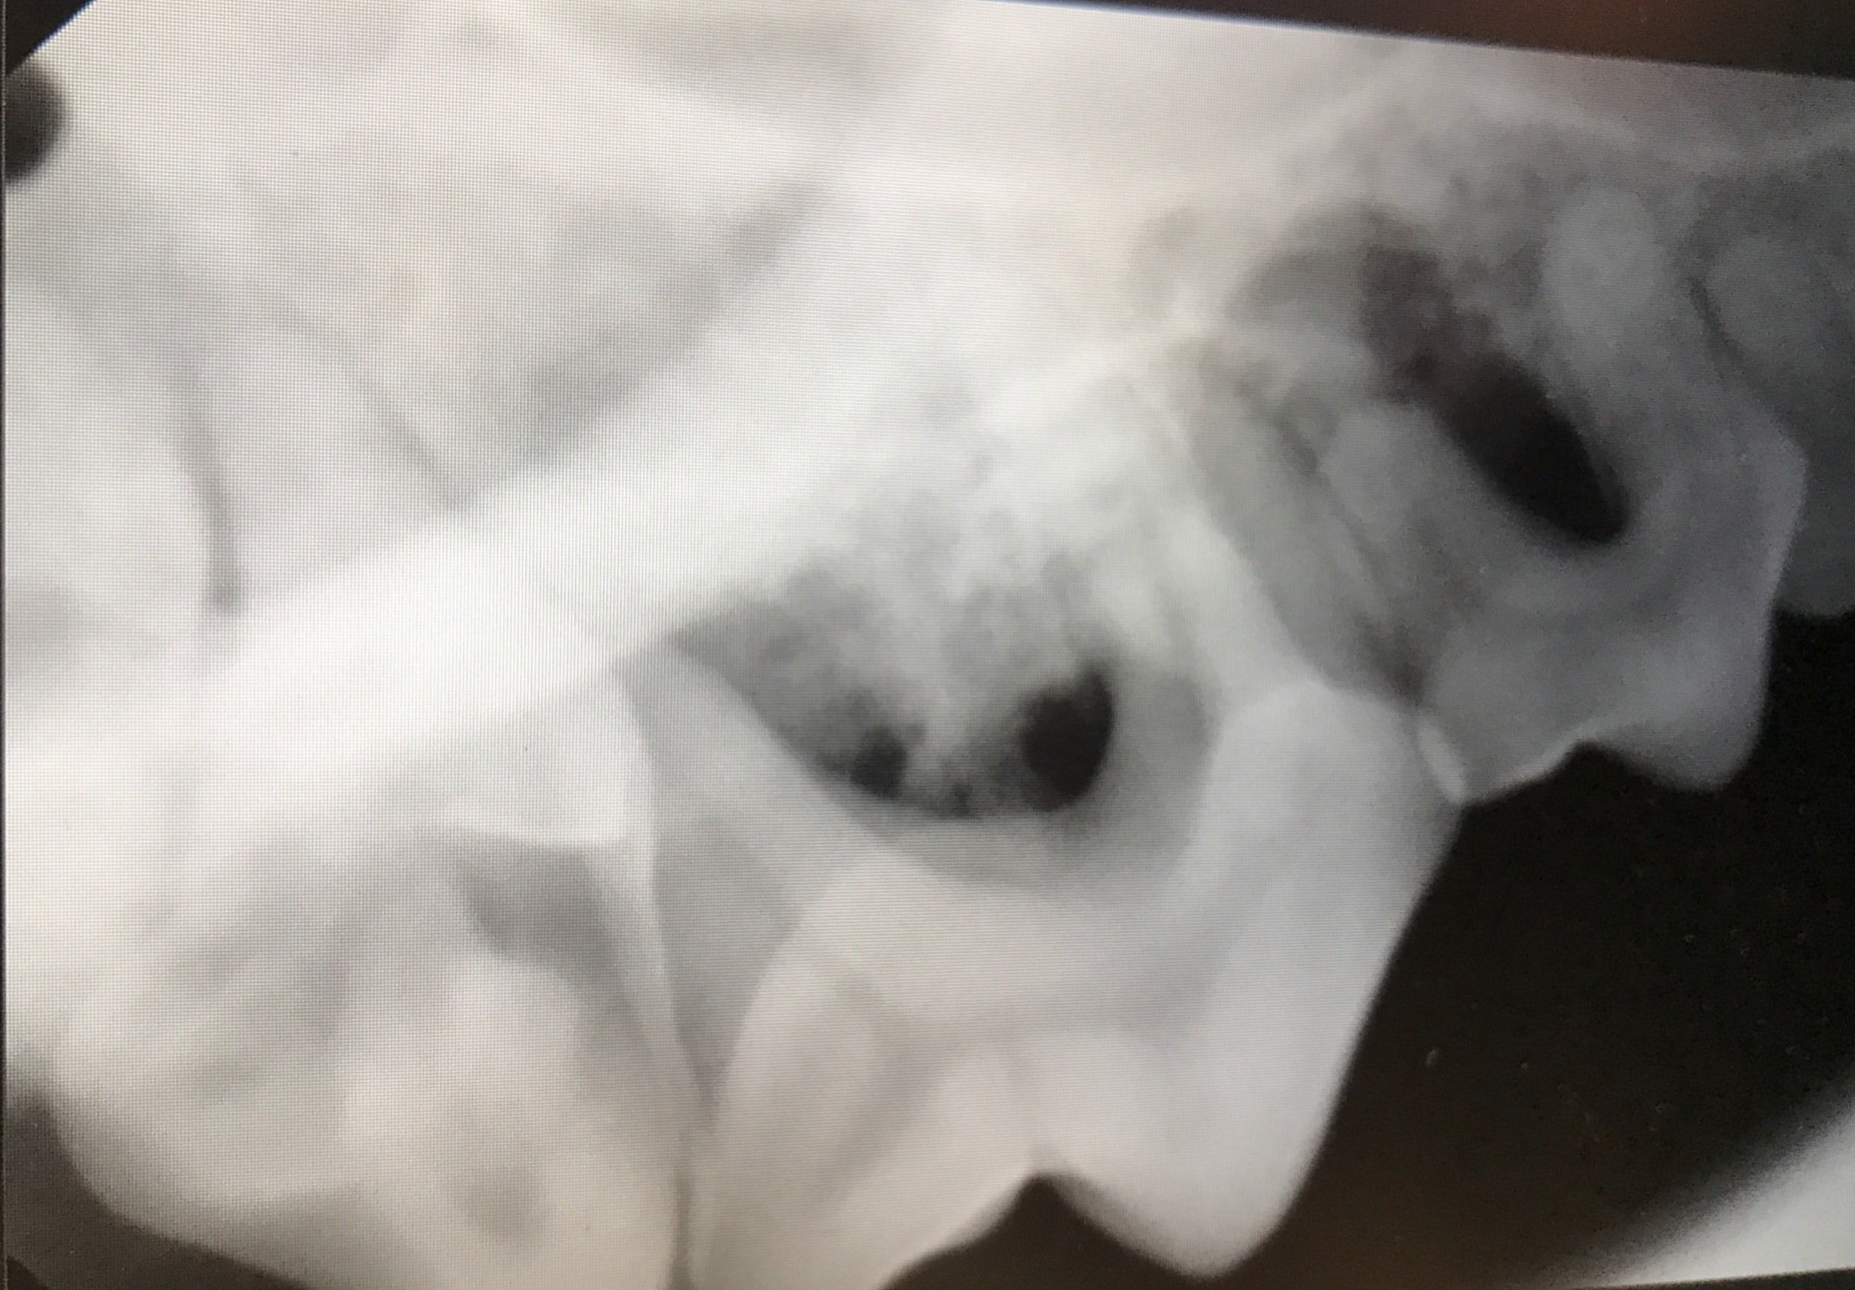

Wortelpunten verwijderen, na een niet goed uitgevoerde totale gebitsextractie, bij de kat

Op foto 2 en 4

zie je de röntgenfoto's waarop nog allemaal kleine stukjes wortel zichtbaar zijn. Door een eerdere, niet goed uitgevoerde, behandeling zorgen zij voor het blijven bestaan van de tandvleesontsteking. Zeker bij een kat met dit probleem is het super belangrijk alle elementen volledig te verwijderen!